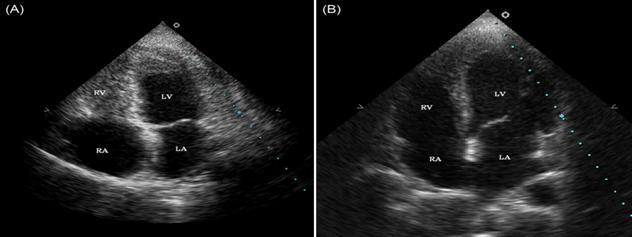

Quan điểm và nhìn nhận trước đây, chúng ta chỉ nghĩ rằng hội chứng Loffler liên quan đến ký sinh trùng trên phổi và hệ hô hấp, trong khi đó chúng còn gây hội chứng này tại nội tâm mạc (endocarditis Loffler’s syndrome) nữa (xem hình ảnh).

Mặc dù hôi chứng Löffler chỉ mô tả trong các trường hợ viêm phổi có tăng bạch cầu ái toan trong bệnh cảnh nhiễm trùng, nhiều tác giả đã cho ra thuật ngữ "Löffler's syndrome" đối với bất cứ thể viêm phổi tăng bạch cầu ái toan nào khởi đầu cấp tính dù có bệnh lý nền thế nào chăng nữa. Nếunguyên nhân không biết, người ta thường goii một cách chung chung là "simple pulmonary eosinophilia". Các tổn thương tim bị gây ra bởi các hiệu ứng protein sinh hạt tăng bạch cầu ái toan (eosinophil granule proteins) làm tổn thương được biết như là viêm nội tâm mạc Loffler (Loeffler endocarditis) và có thể gây bệnh lý tăng bạch cầu ái toan tự phát (idiopathic eosinophilia) hoặc tăng bạch cầu ái toan trong đáp ứng với nhiễm ký sinh trùng.